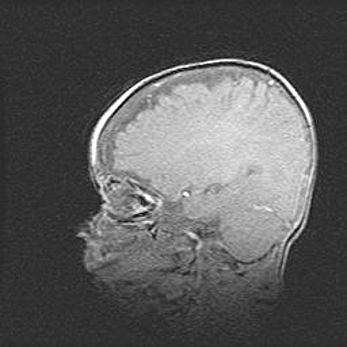

Церебральная ишемия II.

Возраст: 5 дней

Вес: 3400 г

Пол: женский

Окружность головы: 35 см

Срок гестации: 39 недель

Церебральная ишемия – это заболевание, характеризующееся недостаточностью (гипоксией) либо полным прекращением (аноксией) снабжения мозга кислородом по причине закупорки одного или нескольких сосудов. Это приводит к  что метаболическим расстройствам различной степени тяжести в тканях головного мозга, развитию коагуляционных некрозов и гибели нейронов.